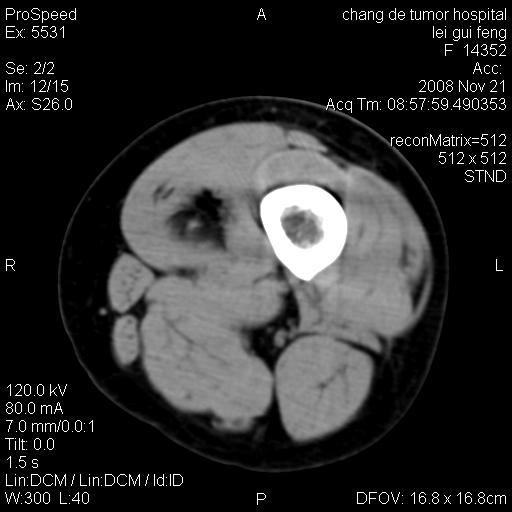

标题: CT16807:女 41 无不适 [打印本页]

标题: CT16807:女 41 无不适

考虑皮样囊肿可能性大

血管瘤可能

血管瘤

血管瘤可能性大!

黏液瘤或表皮杨囊肿

不排除横纹肌肉瘤可能。

血管瘤可能性大或畸胎瘤

考虑脂肪肉瘤

考虑血管瘤可能性大;不排除肉瘤可能。建议行活检。

脂肪肉瘤?

双是软组织肿瘤,病灶内多发钙化,另可见多量脂肪密度影,考虑畸胎瘤,血管瘤,不除外其他